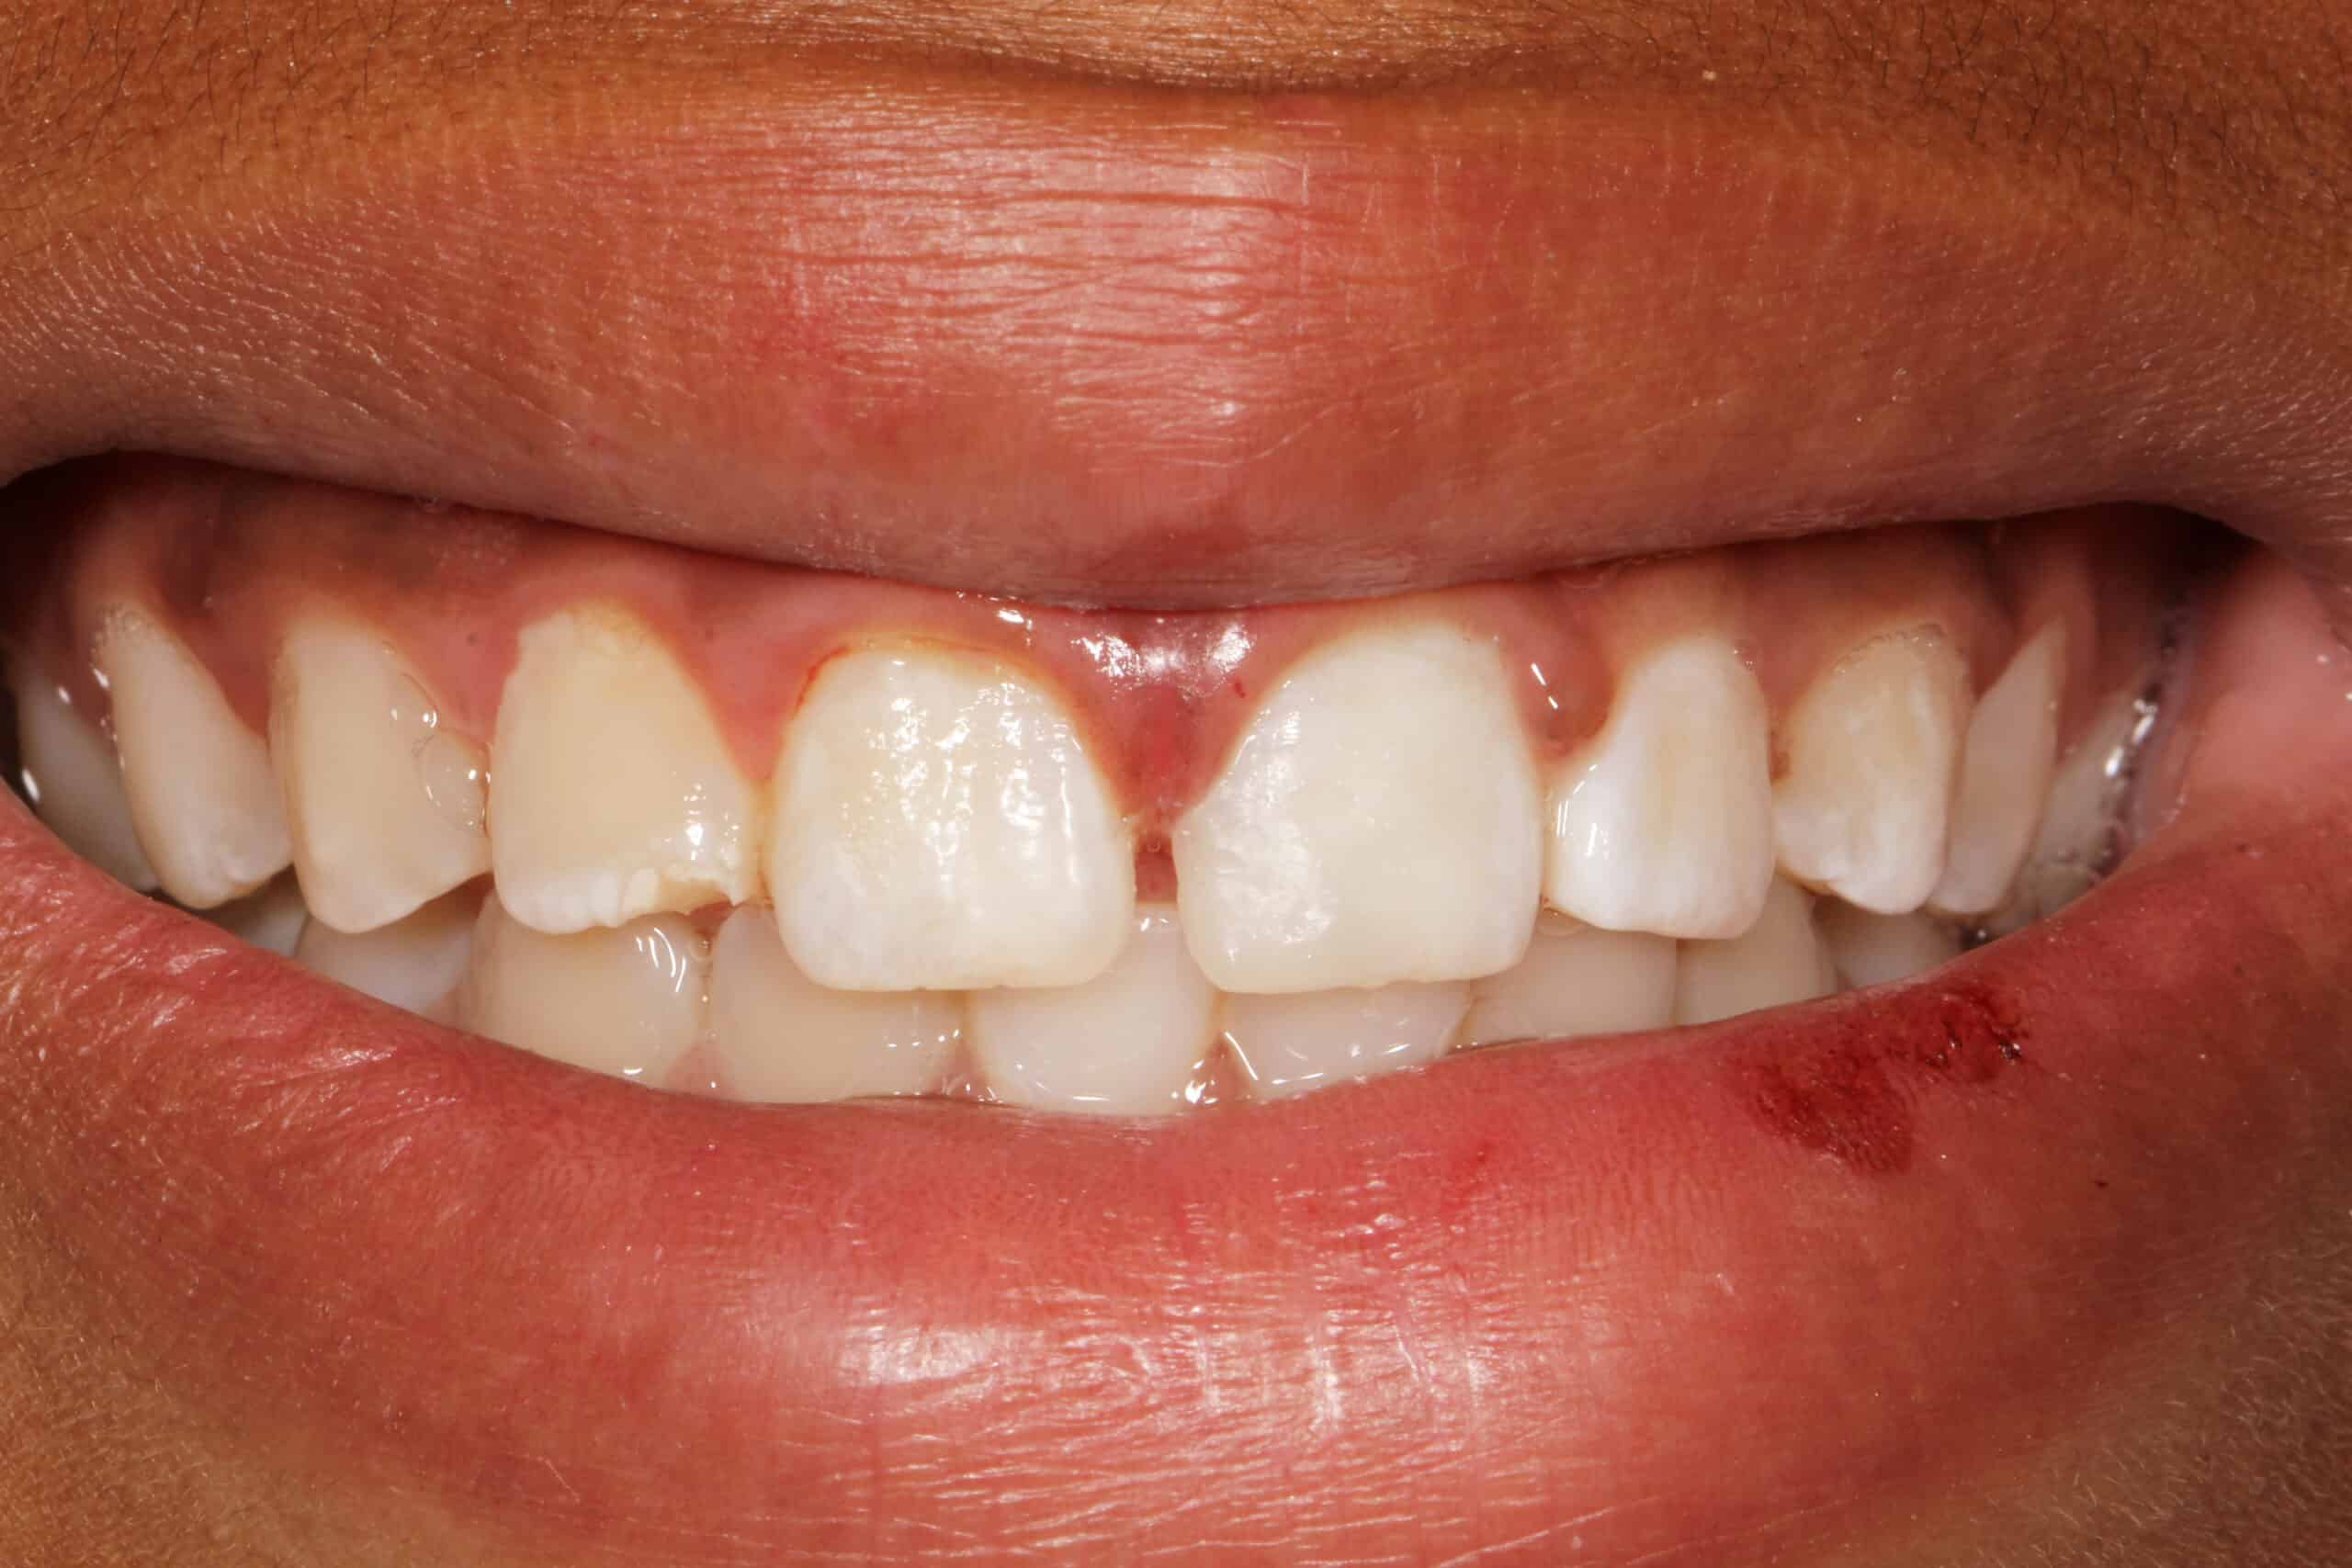

12 year old male patient fell of his bicycle on a Saturday. He hit his lip and front teeth on the pavement. He did not have much tooth pain after the initial trauma. He presented the next day to our office to evaluate the tooth for repair. As an emergency dentist in NYC we treat all types of tooth injuries.

Luckily, his front tooth did not suffer any nerve damage. The tooth was not mobile and mostly intact aside from the obvious fracture. The nerve in the tooth is was healthy, not causing any significant pain.

Since the front tooth did not sustain any nerve damage it was safe to proceed with restoring the tooth with a bonding. A bonding is the same material we often use in dental fillings. We usually do not place porcelain veneers or crowns on patients under 17 years old. Since, young patients’ bone is still growing, the crown may not look correct a few years after placement.

In this case we decided to restore the tooth with dental bonding or filling material. The procedure was performed chair-side in our office with a bit of anesthesia since the tooth was still sensitive from the trauma that it suffered. Patient left our office very happy.